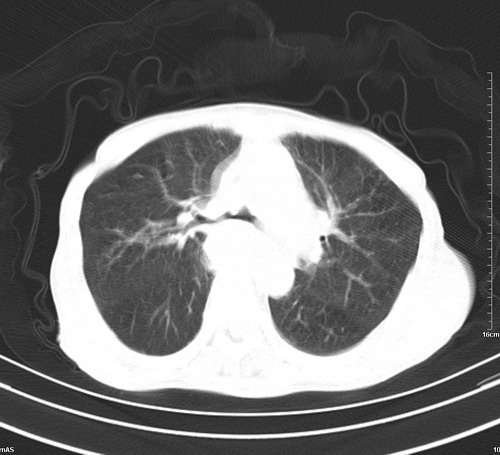

中后纵隔占位,气管、食道受压、变形、移位。恶性可能性大。

后中纵隔团块影,伴气管、食道受压移位,首先考虑转移瘤,肝s5段低密度灶。建议增强检查,另外其结肠是否有问题请提供,右肺部分肺叶局限含气增多,考虑局限肺气肿。

建议强化检查,考虑纵隔型肺癌,小细胞可能性大。

后中纵隔淋巴结肿大,首先考虑转移瘤。